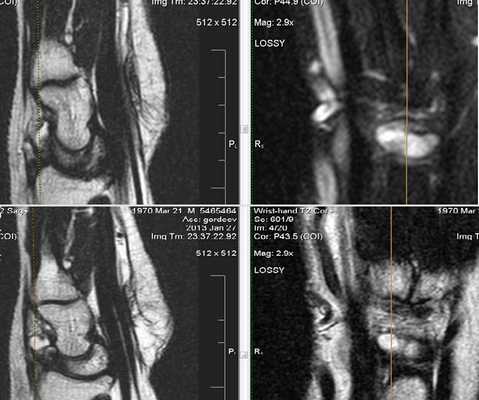

МРТ локтевого сустава в корональной плоскости. В подкожно-жировой клетчатке локтевого сустава отмечаются множественные образования неправильной вытянутой формы, местами сливающиеся между собой — вероятно, венозная мальформация.

МРТ локтевого сустава в сагиттальной плоскости. Отмечается повышенное скопление свободной синовиальной жидкости в полости локтевого сустава. Синовиальная оболочка умеренно гипертрофирована.

а) МРТ локтевого сустава в аксиальной плоскости

б)МРТ локтевого сустава в корональной плоскости. Общее сухожилие разгибателей в месте прикрепления к латеральному надмыщелку плечевой кости неравномерно утолщено, МР-сигнал от него неоднородно повышен на PD FS-ВИ и Т2-ВИ за счет выраженного отека и разволокнения (признаки латерального эпикондилита), общая целость его не нарушена. Окружающие мягкие ткани с признаками отека.